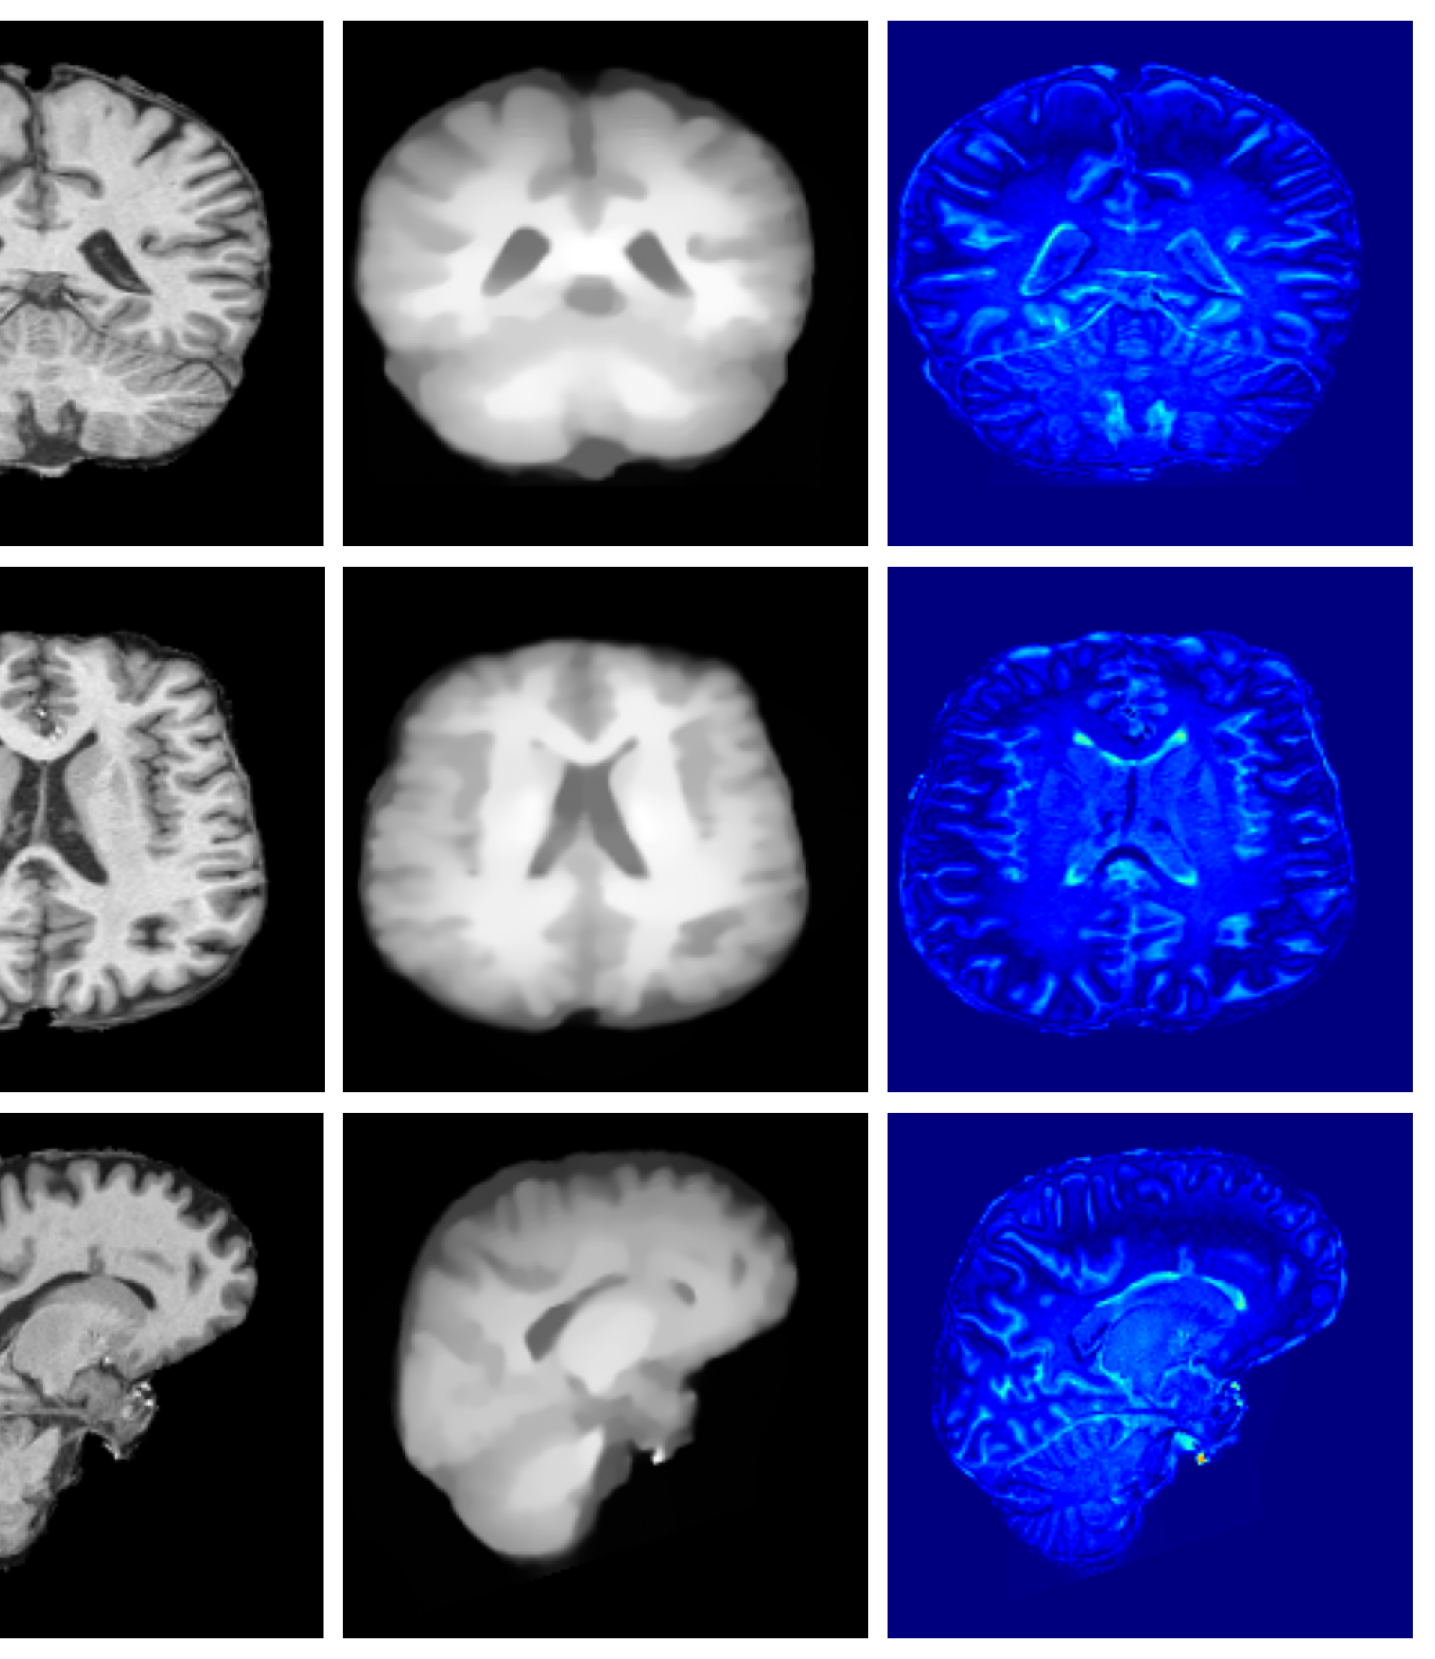

Training. To train our prior, we create a diverse cohort of 7383 high-quality, quality-controlled 1 mm isotropic MRI scans, comprising of 5279 T1-weighted (T1w), 1516 T2-weighted (T2w), and 588 FLAIR images from public datasets; ADNI Weiner2017, HCP Essen2012, Chinese HCP Yang2024, ADHD200 Brown2012, AIBL Fowler2021, COBRE sidhu2018 MCIC gollub2013, ISBI2015 challenge and OASIS3 LaMontagne2018. All images are skull-stripped, bias-field corrected, and affinely registered to an atlas template. Detailed processing steps are available in Appendix A.2.

For both the Clinical and Low-field datasets, low-resolution images are skull-stripped and normalized to [-1, 1]. The alignment to MNI space is required by forward model given in Equation 11 and is achieved by recomputing the affine transformation through centroid alignment of anatomical labels from SynthSeg Billot2023 segmentations with the corresponding atlas centroids. Example low-resolution images are shown in Figure 6.

A.8 Additional qualitative restoration results

Additional qualitative results for the Clinical dataset are given in Figures 7, 8 and 9, and for the Low-field dataset in Figures 10 and 11.